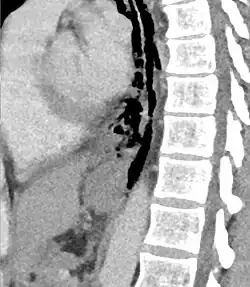

The diagnosis of Boerhaave syndrome is suggested on the plain chest radiography and confirmed by chest CT scan. The initial plain chest radiograph is almost always abnormal in patients with Boerhaave syndrome and usually reveals mediastinal or free peritoneal air as the initial radiologic manifestation. With cervical esophageal perforations, plain films of the neck show air in the soft tissues of the prevertebral space.

Hours to days later, pleural effusion(s) with or without pneumothorax, widened mediastinum, and subcutaneous emphysema is typically seen. CT scan may show esophageal wall edema and thickening, extraesophageal air, periesophageal fluid with or without gas bubbles, mediastinal widening, and air and fluid in the pleural spaces, retroperitoneum or lesser sac.